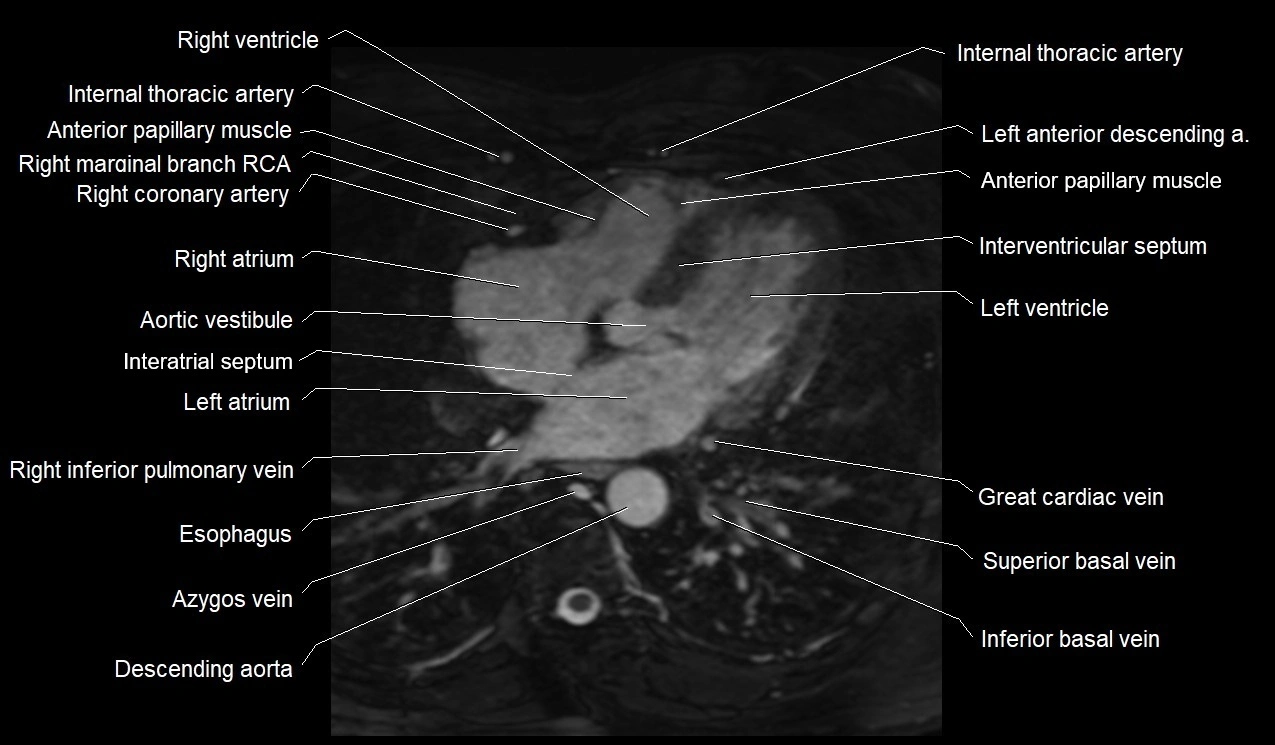

- Anterior papillary muscle

- Aortic vestibule

- Great cardiac vein

- Interatrial septum

- Interventricular Septum

- Left anterior descending artery (LAD)

- Left internal thoracic artery

- Left ventricle

- Right atrium

- Right inferior pulmonary vein

- Right ventricle